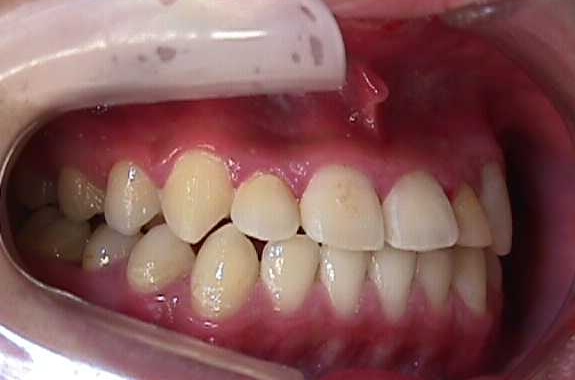

【矯正症例】左上2番3番逆転症例2

Before

After

左上2番3番逆転症例

随分、前の症例で現在、写真しか残っておりません。

治療費や、治療期間を掲載できないことをご了承ください。

私の矯正歯科医の人生の中でも、特に思い出深い症例です。